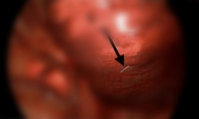

“배 아프고, 소변도 안 나와”… 알고 보니 ‘이것’ 삼킨 게 원인이었다